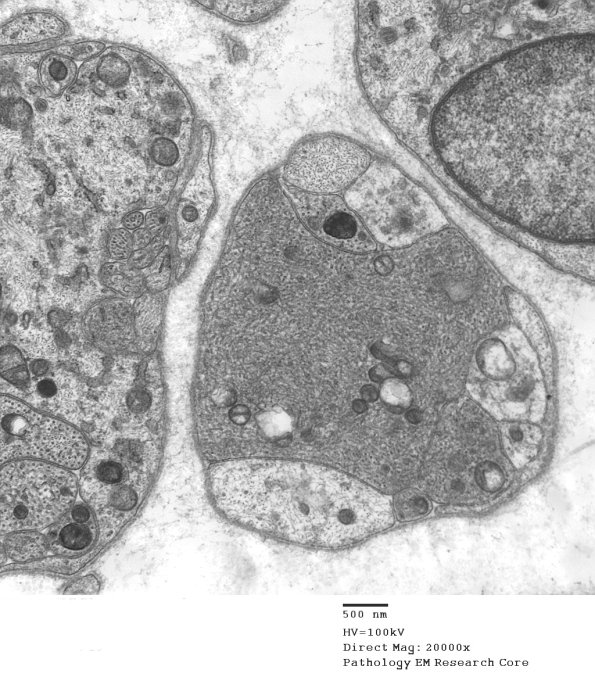

Particularly dense aggregates consist of tubulovesicular processes. (electron micrographs)